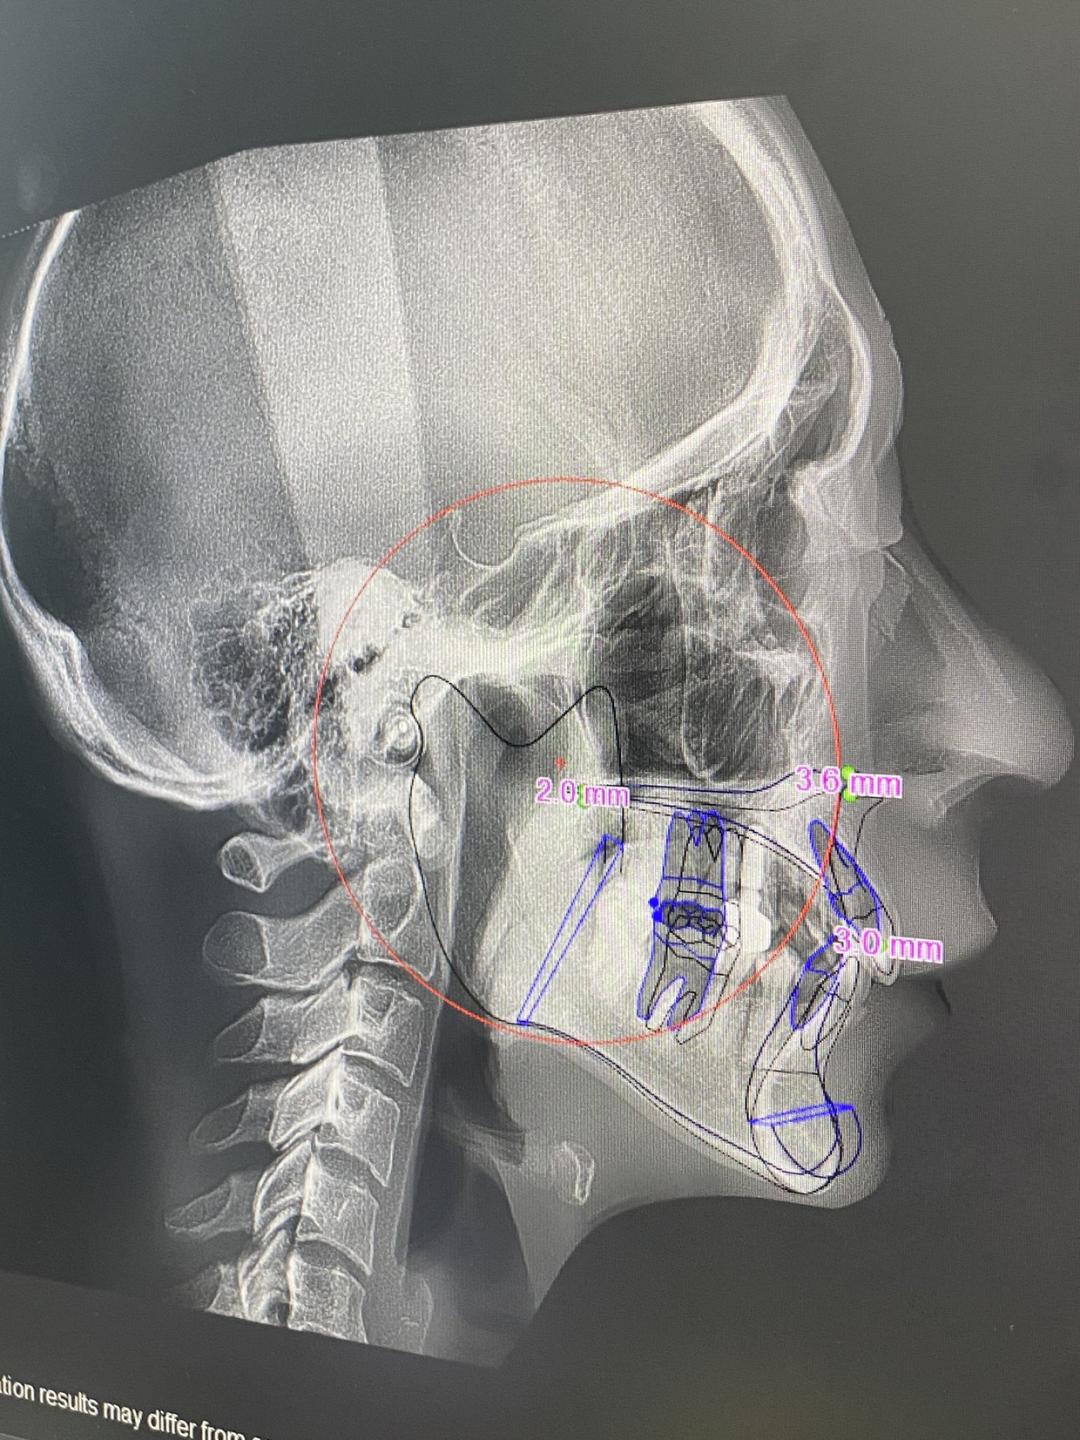

做完上颌、下颌和脸部轮廓的手术,脸最肿的时候,连带鼻子和嘴里都肿,呼吸都不顺畅,吃个饭更是要了老命。